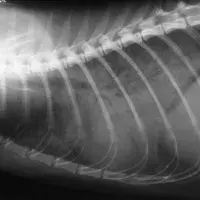

A range of resources for referring vets to use in diagnosing and treating mycobacteria cases. ResourcesIdentificationIf you think you may have seen a case but aren’t sure, our flow chart may help with diagnosis. You may also find our background and clinical presentation resource useful.TestingThere are there 3 tests we use to try to identify the species of mycobacteria present in a patient; PCR, the IGRA blood test and specialist culture. Please read about these different tests, how they are most usefully used and ideas of costs: Testing for Feline (or Canine) Mycobacterial Infections.The PCR test is run by Leeds University Teaching Hospital and the submission address and form can be downloaded from this link. This only takes 1-2 weeks to get the result and gives you the exact species of mycobacteria involved.The IGRA is offered by Biobest Laboratories here in Edinburgh and the test sample requirements and submission form can be found on their website: https://biobest.co.uk/companion-animal-diagnostics. This assay is very good at detecting an immune response to mycobacteria that cause TB; these are responsible for ~50% of all mycobacterial disease in cats in the UK.APHA also offer specialist culture, but it only detects ~50% of cases, and can take up to 6 months to get an answer, especially with M. microti, which is the most common Mycobacteria found to cause disease in cats.Post-diagnosisThe presence of mycobacteria within a tissue sample is often flagged up on a histopathology report. They are seen as acid fast Ziehl Neelson (ZN) positive bacteria with the conformation of mycobacteria. If the biopsy finds these you now need to know whether it is a tuberculous (TB) causing mycobacteria – Mycobacteria tuberculosis complex (MTBC) – or a non-tuberculous mycobacteria (NTM). If you have diagnosed a case of mycobacterial infection in a companion species, then a lot of questions can be answered by reading Companion Animal Mycobacterial Infections: Treatment and Zoonotic risks in addition to Treating Mycobacterial infections in Cats – Drugs, Doses & Costs. This contains useful background information on disease epidemiology, common clinical presentations, diagnostics and first-line treatment. We have also prepared an owner information sheet.Advice & ReferralIf you are a veterinarian requiring further advice on a patient that is not answered in the documents above, the team at the University of Edinburgh can assist. For advice requests, complete a referral advice form and email it to companion.animalTB@ed.ac.uk. Please note that there is usually a charge for this service to cover the clinician time.To refer a patient with suspected or confirmed mycobacterial infection to our team, please contact our Reception directly hfsareception@ed.ac.uk or complete an online referral request form. We have also prepared an owner information sheet.When treating cases, please read our information sheet about treatment protocols and the potential side effects of these drugs. For cases of TB in cats, when caused by either M. bovis or M. microti, and presenting with cutaneous lesions and/or lung involvement we now have ~80% susses rate when treating these cases.There will be a charge for this advice.Mycobacterial Disease Advice Request FormFurther readingCompanion Animal Mycobacterial Infections: Further ReadingThank you to everyone who has shared cases with us previously, especially those who have given us residual blood samples, biopsies, photographs and radiographs of your patients. This article was published on 2024-09-02